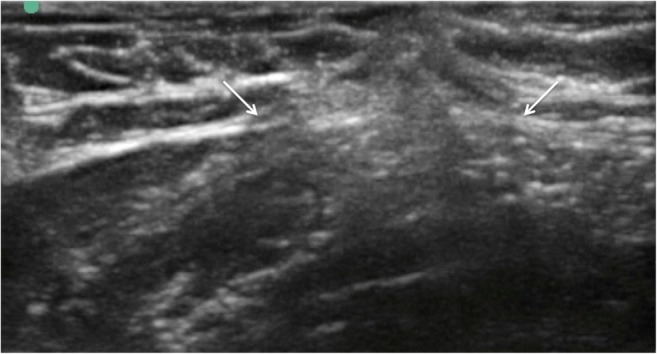

Fig. 8.

Ultrasound image of fascial layer post thread release demonstrating divided and retracted fascial edges (white arrows)